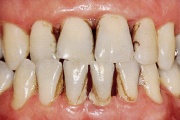

Vali sind huvitav pilt ja me näitame sellega seotud haigust ja sümptomeid